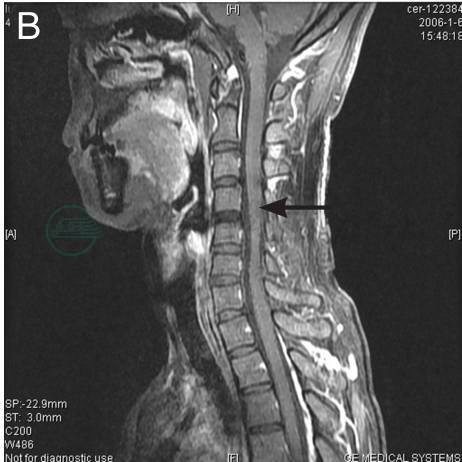

颈髓MR示

在自然位置状态下显示C5~7轻度萎缩、T2WI见髓内条状高信号;颈部屈曲位置状态下,可见硬膜囊向前移位,脊髓无明显受压,但前后径变扁(图1);C5~7硬膜外间隙在T1WI与脊髓等信号、T2WI呈高信号,注射造影剂后呈均匀一致强化,回到自然位置状态下该信号即消失(图2)。

图1 A:正常位T1示显示C5~7轻度萎缩;B:正常位T2示C5~7髓内条状高信号;C:屈颈位T1;D:屈颈位T2